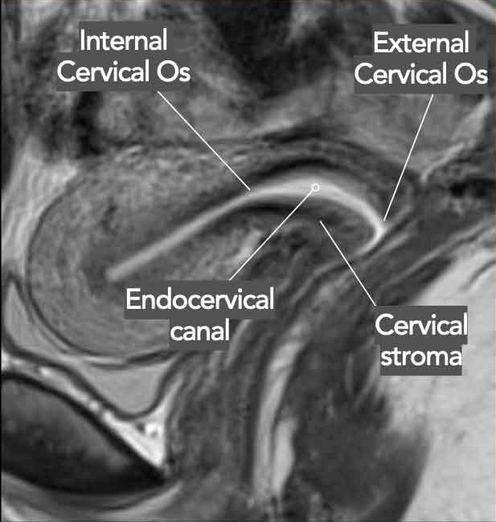

• Distance of mass from cervical os

• 2B - Tumor invasion beyond the uterus with para-metrial invasion (basically dark circular border of cervix) - see image —>